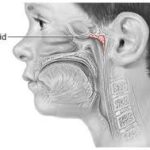

Adenoid dokusu nasofarenkste, Östaki borusunun açıldığı bölgeye yakın bulunur.

Östaki borusunun farengeal açıklığı direkt olarak mekanik olarak tıkanır.

Havalanma bozukluğu: Tıkanmış Östaki borusu nedeniyle orta kulak havası yeterince yenilenemez → basınç eşitsizliği oluşur.

Sıvı birikimi (effüzyon): Negatif basınç, seröz sıvının orta kulağa sızmasına neden olur.

Adenoid hipertrofisi → Östaki borusu açıklığını daraltır

Tıkanan Östaki borusu → orta kulakta negatif basınç oluşur

Negatif basınç → orta kulakta sıvı birikir → işitme kaybı ve tekrar eden otitis media